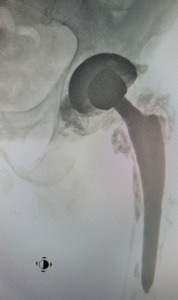

Twenty-seven years later, due to the development of the secondary degenerative disease of the left hip joint, the patient underwent implantation of a total hip joint replacement in which metal/polyethene articulation was used, and ceramic fragments were carefully removed intraoperatively. In this case, a protocol of rinsing the operated joint with an electric pulsation system was used during the revision procedure, as in the case of PJI (periprosthetic infection). Six years after this procedure, the patient was observed to have deformation of the metal head of the endoprosthesis, appearing in control X-rays with relatively minor changes in the thickness of the polyethylene (acetabular insert). The head deformation was accompanied by defects that were visible in the form of radiolucencies located in the third, closer to the femur and in the area of the lower pole of the acetabulum (Fig. 2). The patient reported increasing pain in the left hip joint (increasing with weight bearing), and therefore qualified for revision surgery. The examination revealed severe macroscopic deformation of the metal head of the endoprosthesis, the formation of extensive defects in the proximal part of the femur (greater and lesser trochanter), with perforation of the femur and loosening of the stem of the primary endoprosthesis, as well as bone cysts in the periacetabular area (without destabilisation). The cavities were filled with dark content (specific to metal abrasion products), indicating severe metallosis and the metal neck of the femoral stem was severely scratched. Intense contamination of the polyethylene surface of the insert of an unknown origin was also observed (Fig. 3,4). The elements of the primary endoprosthesis removed during the procedure were subjected to further macroscopic and microscopic examination.

The macroscopic analysis revealed that the polyethylene surface was contaminated with particles of different sizes embedded in the endoprosthesis cup’s sliding surface. A sample stereoscopic image of such particles is presented in Figure 5. Observations at higher magnifications showed that their embedding in the surface was related to the formation of numerous cuts in the polyethylene surface, which proves their deep anchoring in the polyethylene surface. A similar macroscopic image of ceramic particles embedded in the surface of the polyethylene insert, formed after the fracture of the ceramic head of the endoprosthesis, was observed by Kampf et al.22 And Hasegawa et al.23 In the first case, this led to dramatic wear of the steelhead of the endoprosthesis, which corresponded to a weight loss of 48.1g in the form of outstanding steelwear products released into the surrounding tissues.22